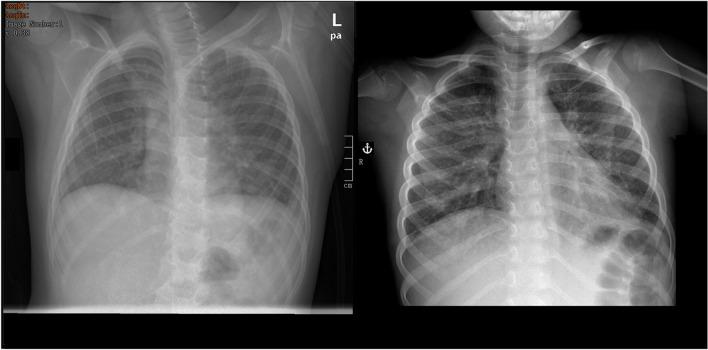

A boy with known autism spectrum disorder was transferred to our department due to a rapidly worsening respiratory situation. The patient's history revealed previous treatment with albendazole against a Toxocara infection 2 weeks prior in Poland. Blood analysis showed such severe eosinophilia and markedly elevated levels of IgE that, initially, a hematologic malignancy was suspected. However, diagnostic workup including autoimmune diagnostic, molecular genetic testing, fluorescence in situ hybridization (FISH), bone marrow aspiration, and parasitological testing led to the diagnosis of an insufficiently treated Toxocara infection. Treatment with albendazole and prednisone (six cycles for 4 weeks each) was administered. This treatment regime led to prompt improvement of symptoms and normalization of laboratory findings.

一名已知患有自闭症谱系障碍的男孩因呼吸状况迅速恶化而转入我科。患者病史显示,两周前在波兰曾接受过阿苯达唑治疗弓首线虫感染。血液分析显示严重的嗜酸性粒细胞增多和显著升高的 IgE 水平,最初怀疑为血液系统恶性肿瘤。然而,包括自身免疫诊断、分子遗传学检测、荧光原位杂交(FISH)、骨髓抽吸和寄生虫学检测在内的诊断性检查导致诊断为治疗不充分的弓首线虫感染。给予阿苯达唑和泼尼松(每个周期 4 周,共 6 个周期)治疗。该治疗方案迅速改善了症状并使实验室检查结果正常化。